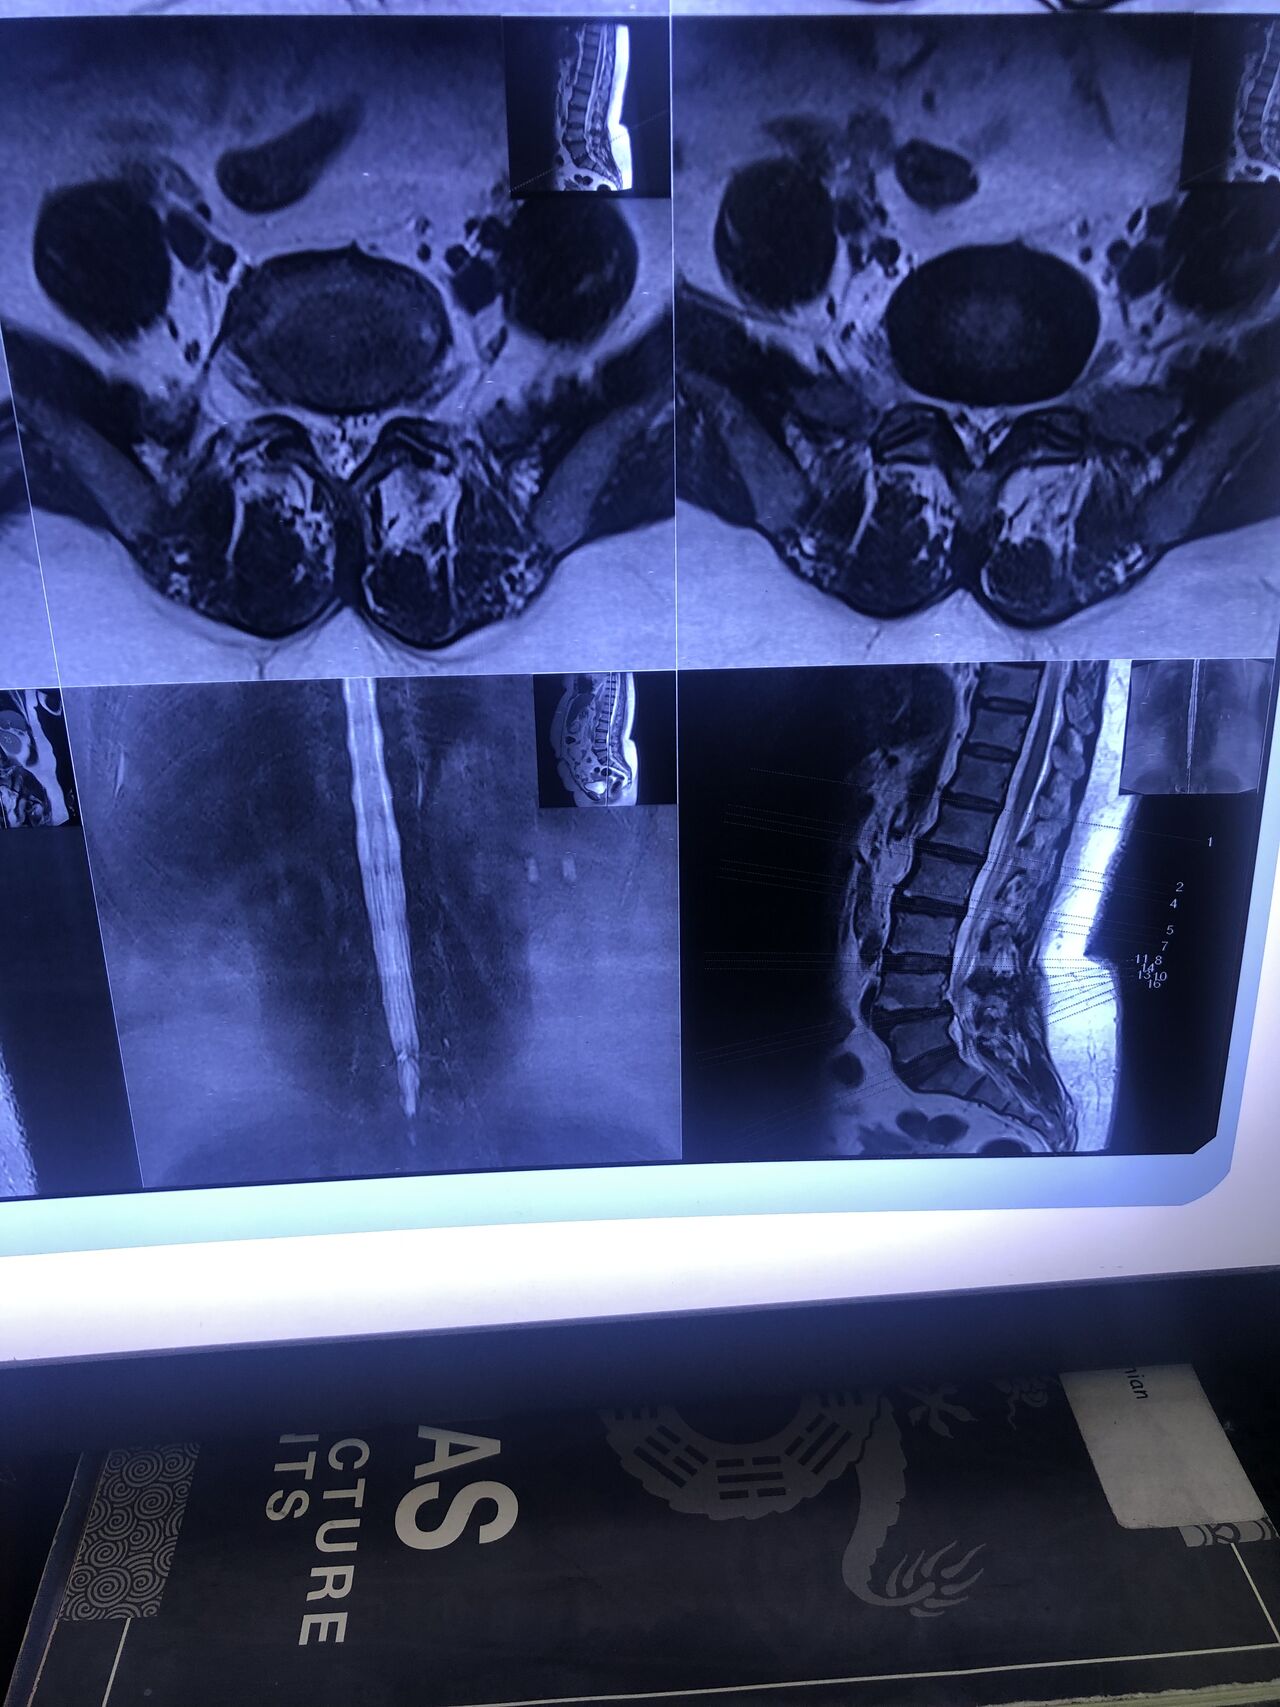

L4-L5 level:

sever L4-5 canal stenosis mainly due to FL hypertrophy?

CSF block. Mild L3 retrolisthesis, facets hypertrophy bilateraly causing L and R IVF stenosis, disc hyperbule

Since I’ve noticed instability in some segments I asked for dynamic L/S x ray:we see mild L4 ant listens due to DjD/DDD. There is not any pars defect.

In cervical mri I marked some findings plus their reports

I will give her treatment via Cox chiropractic flex dis and axial decompression. I would use DTS decompression

Since there is a few mild to moderate DjDs/ DDs in her lower back I won’t use lumbar adjustment on her